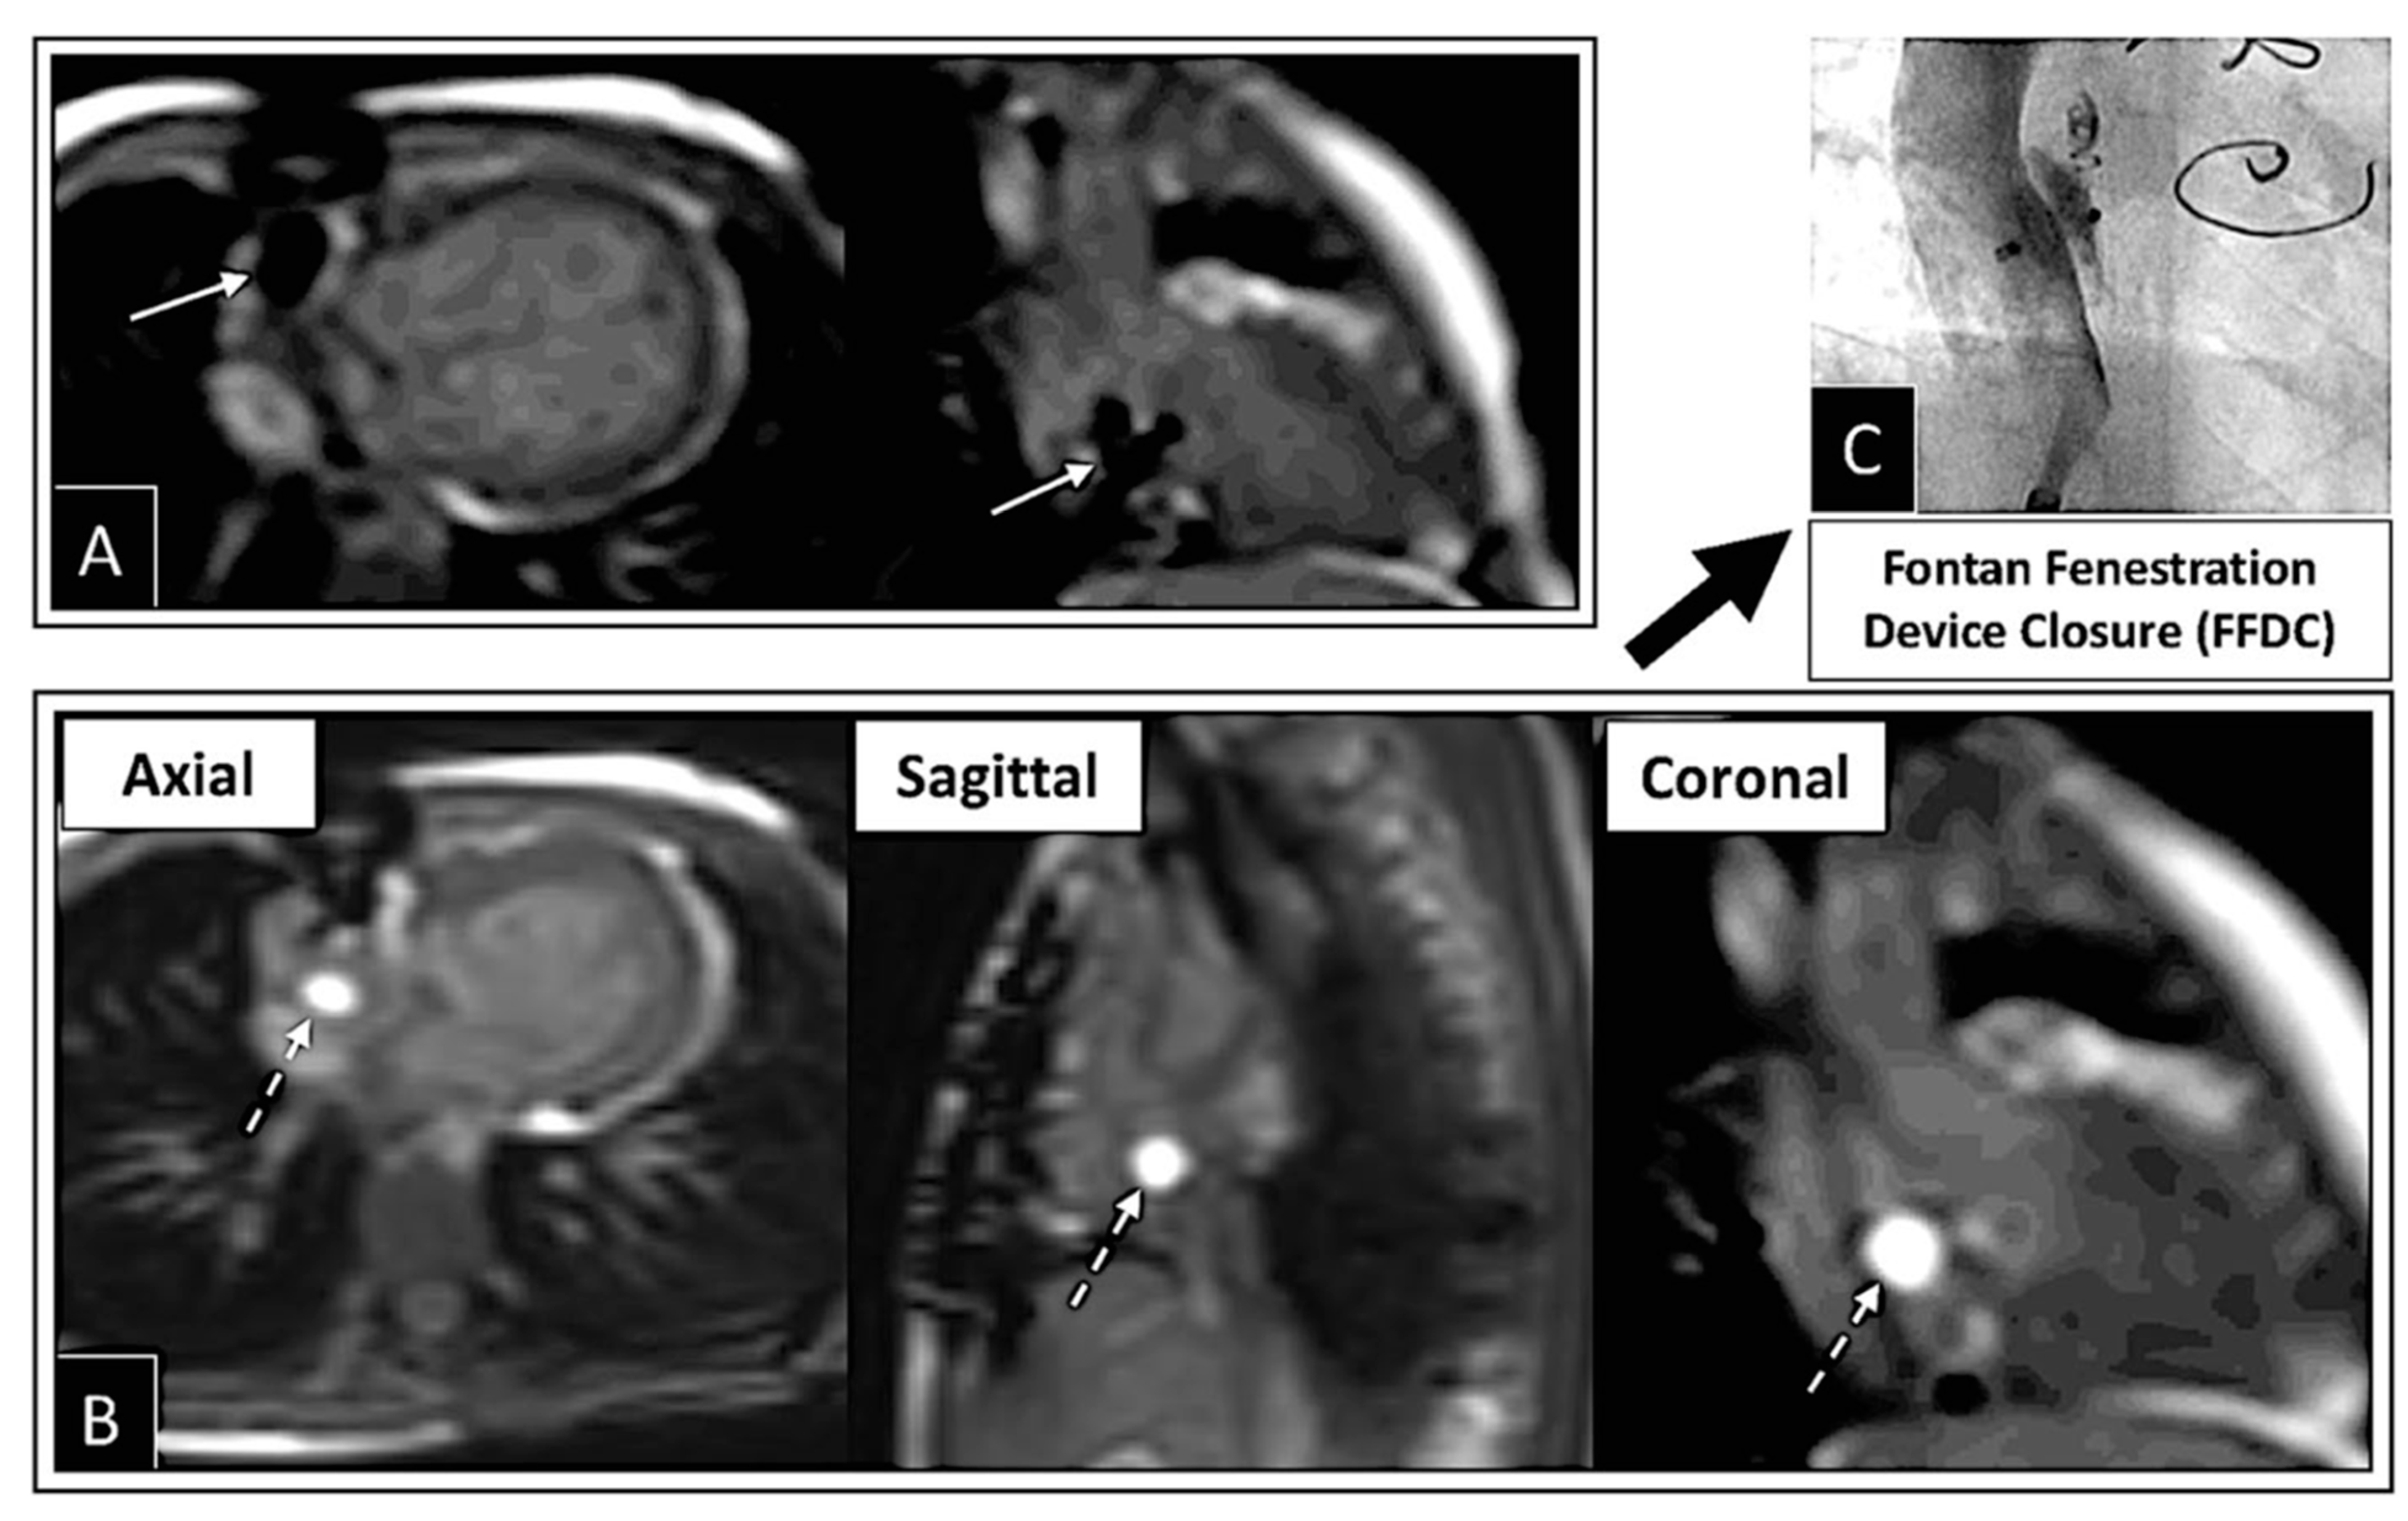

| Fontan Fenestration Test Occlusion | FFTO |

| Fontan fenestration device closure | FFDC |